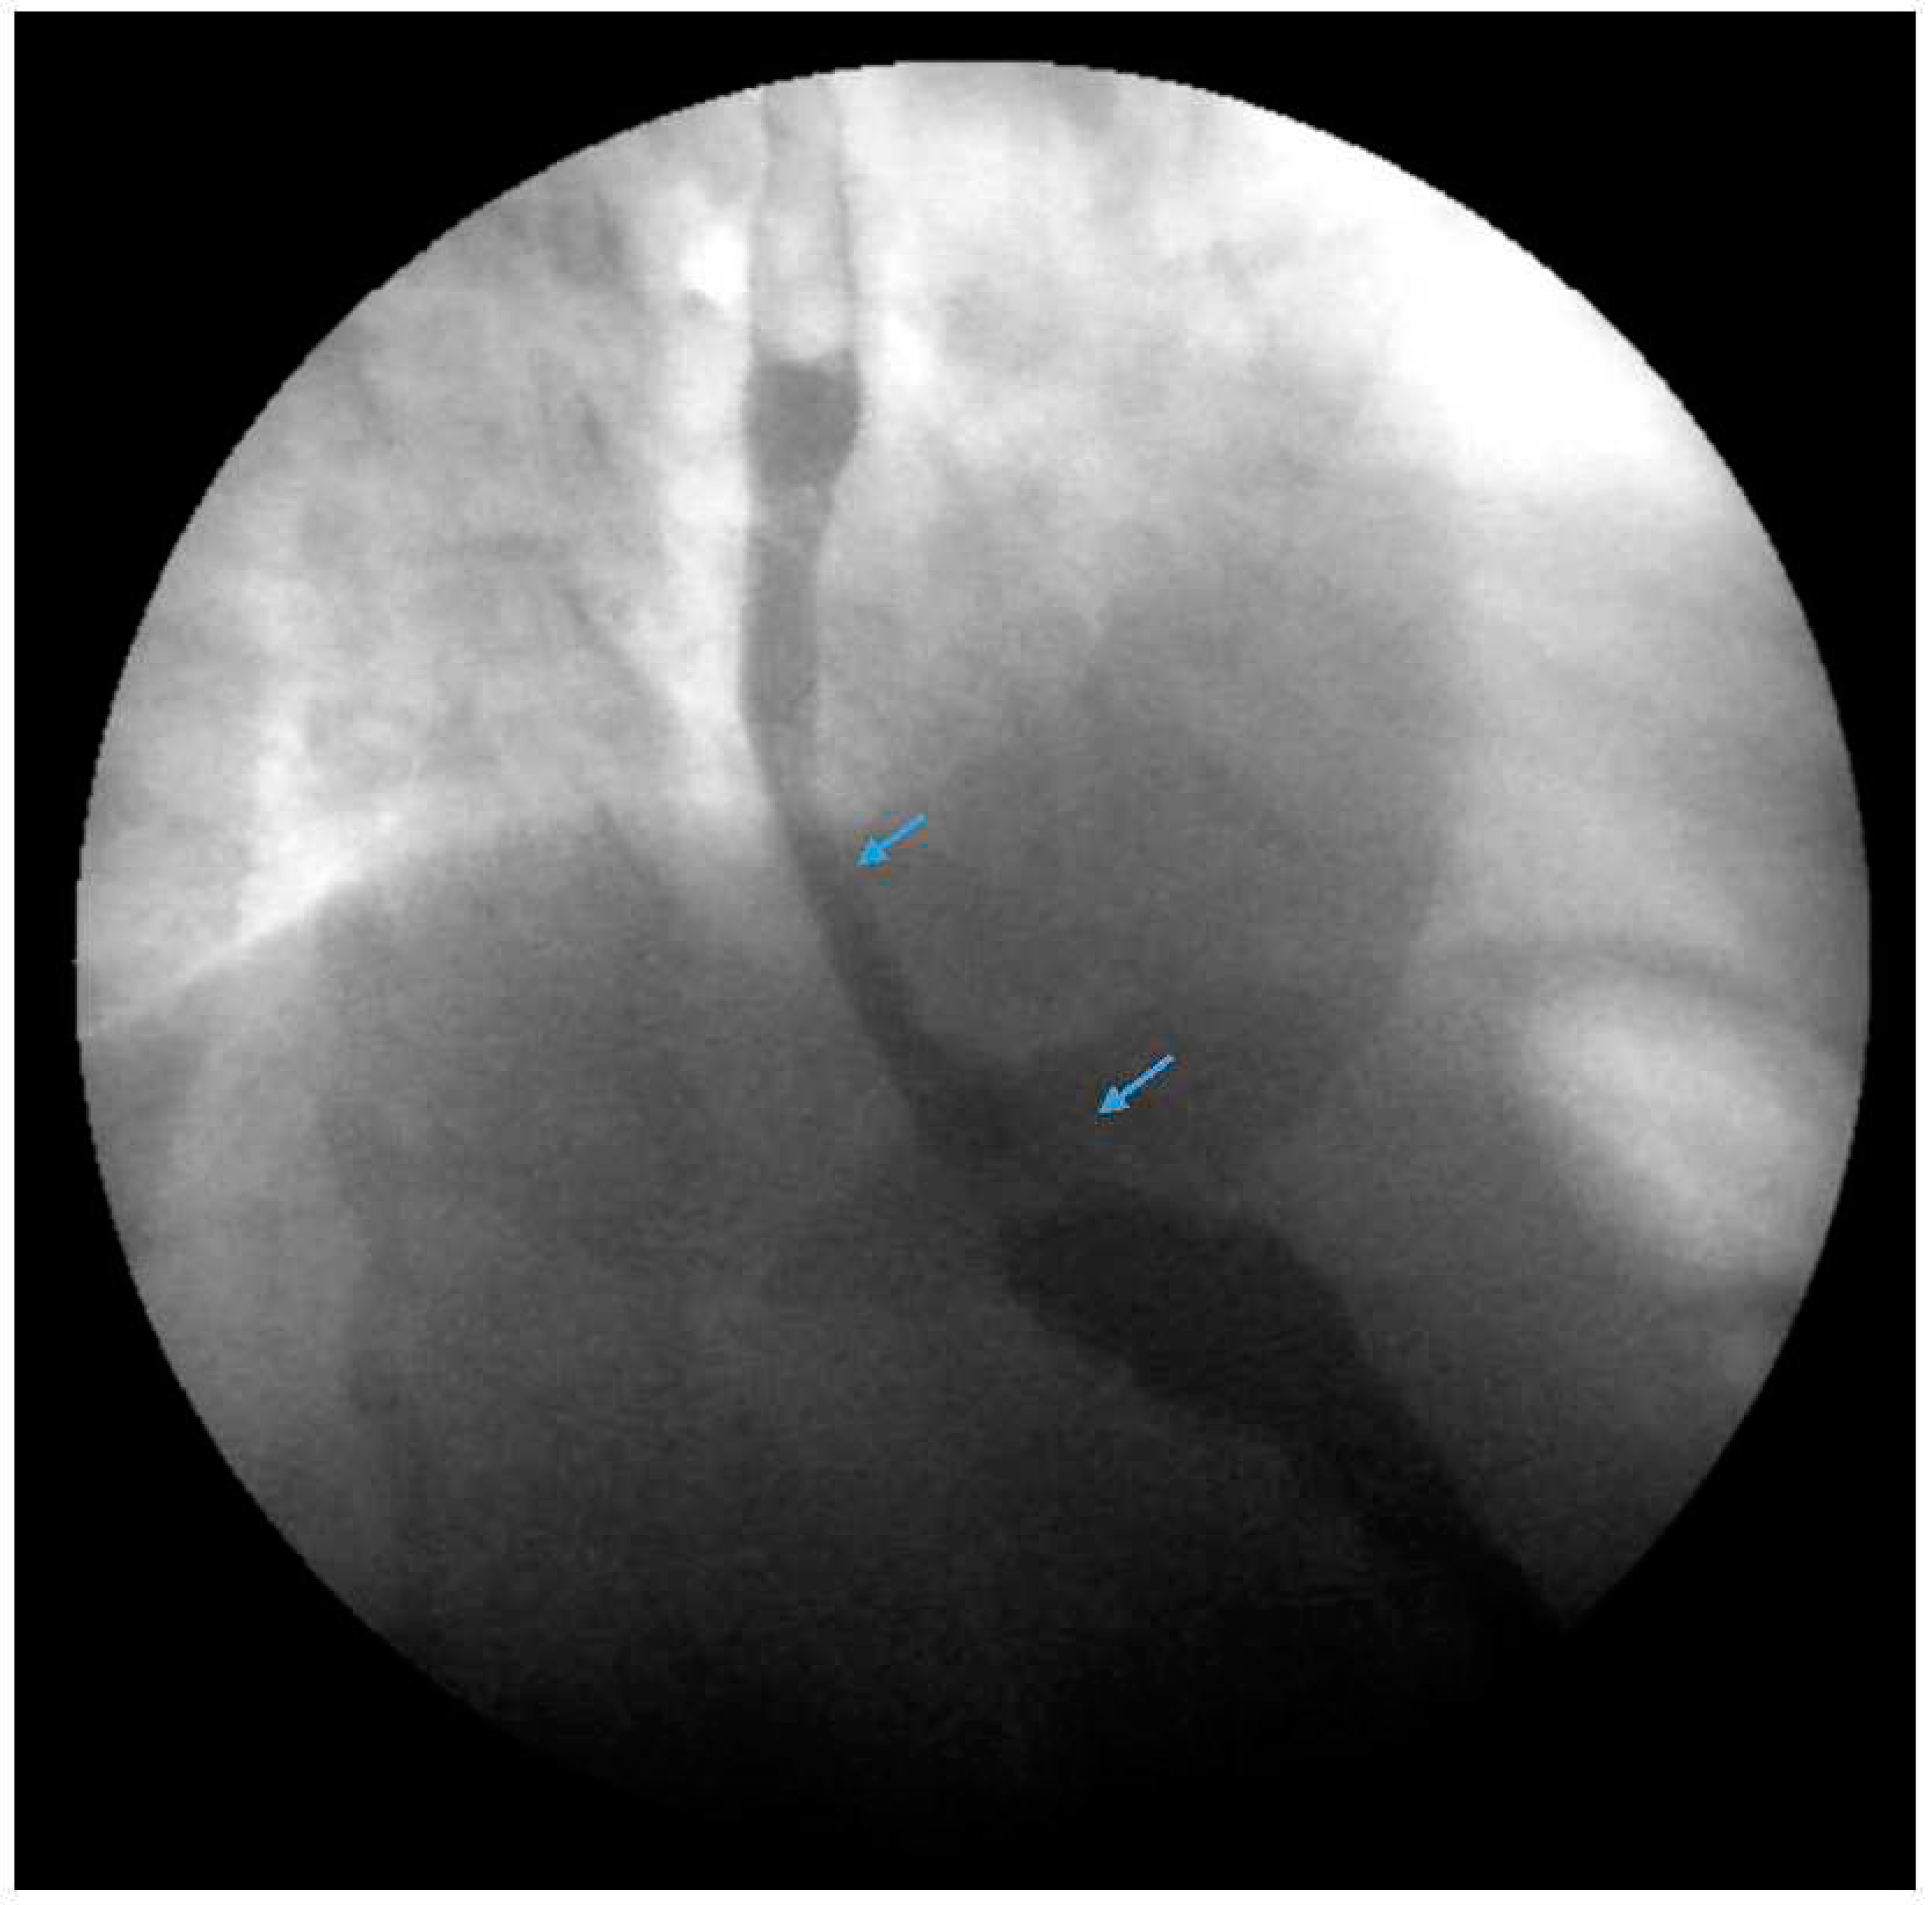

Figure 2. An upper gastrointestinal series reveals a moderate, sliding type one hiatal hernia (bottom arrow) in addition to gastroesophageal reflux disease (top arrow) in a patient with morbid obesity.